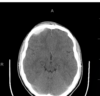

Which of the following mechanism of TBI is depicted in the CT?

1- Skull fracture

2- Contusion (bruise)

3- hematomas (blood clots)

4- lacerations (tear)

5- Diffuse axonal injury (nerve damage)

A